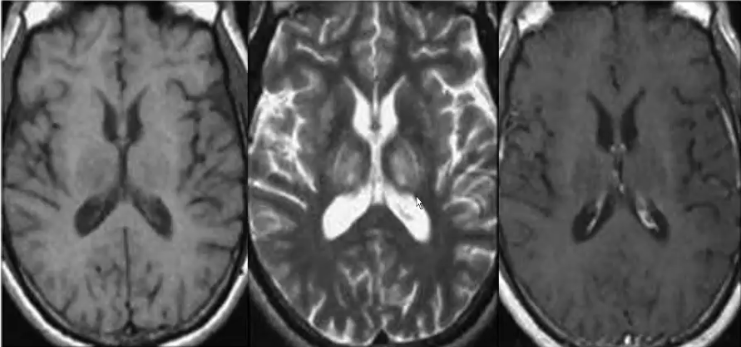

❖ MR表现:病灶大部分为T2不均匀高信号,呈条纹状改变;少部分T2W为低信号,可能由多种离子尤其是铁离子过度沉积所致。T1信号常降低,但是由于铜的顺磁性,T1的信号亦有可能升高。对比增强无明显强化,在疾病早期可有弥散受限,随着组织坏死和海绵状组织降解,弥散相可能恢复正常。